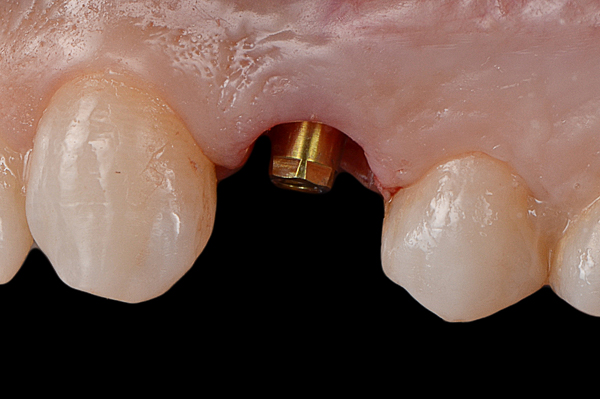

Il caso presenta la riabilitazione di un premolare superiore interessato dal fallimento di un trattamento endodontico in una paziente donna di 37 anni, non fumatrice e con una buona igiene.

A seguito dell'analisi radiografica viene pianificata l'estrazione atraumatica del premolare con l'inserimento contestuale di un impianto Shelta. La riabilitazione immediata viene eseguita con un pilastro XA per protesi avvitata, su cui viene fissato un provvisorio realizzato in laboratorio secondo i principi dei profili di emergenza della tecnica B.O.P.T.

Donna, 37 anni, non fumatrice, con una buona igiene, si presenta in studio con un fallimento del trattamento endodontico dell'elemento 1.4.